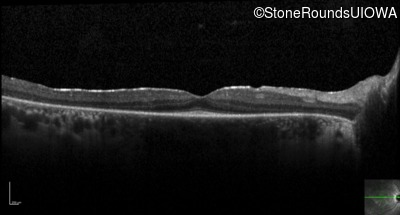

Optical Coherence Tomography - Right -

20/20 -1

Exemplar / OCT Stack

OCT Stack